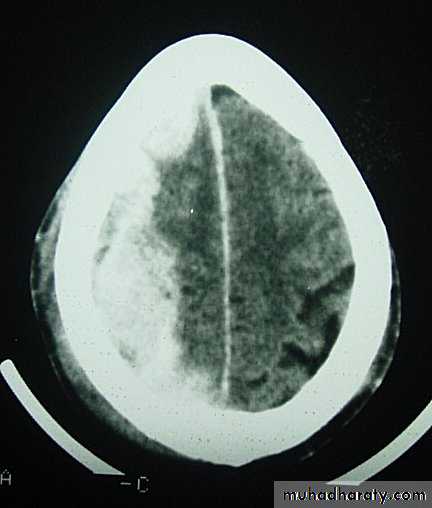

Clinical Picture: patient will present with a picture similar to that of an extradural haematoma, but there is persistent loss of consciousness with no lucid interval.Ct scan will show a concave hyperdence collection because blood follows the subdural space over the convexity of the brain.

Acute Subdural Haematoma